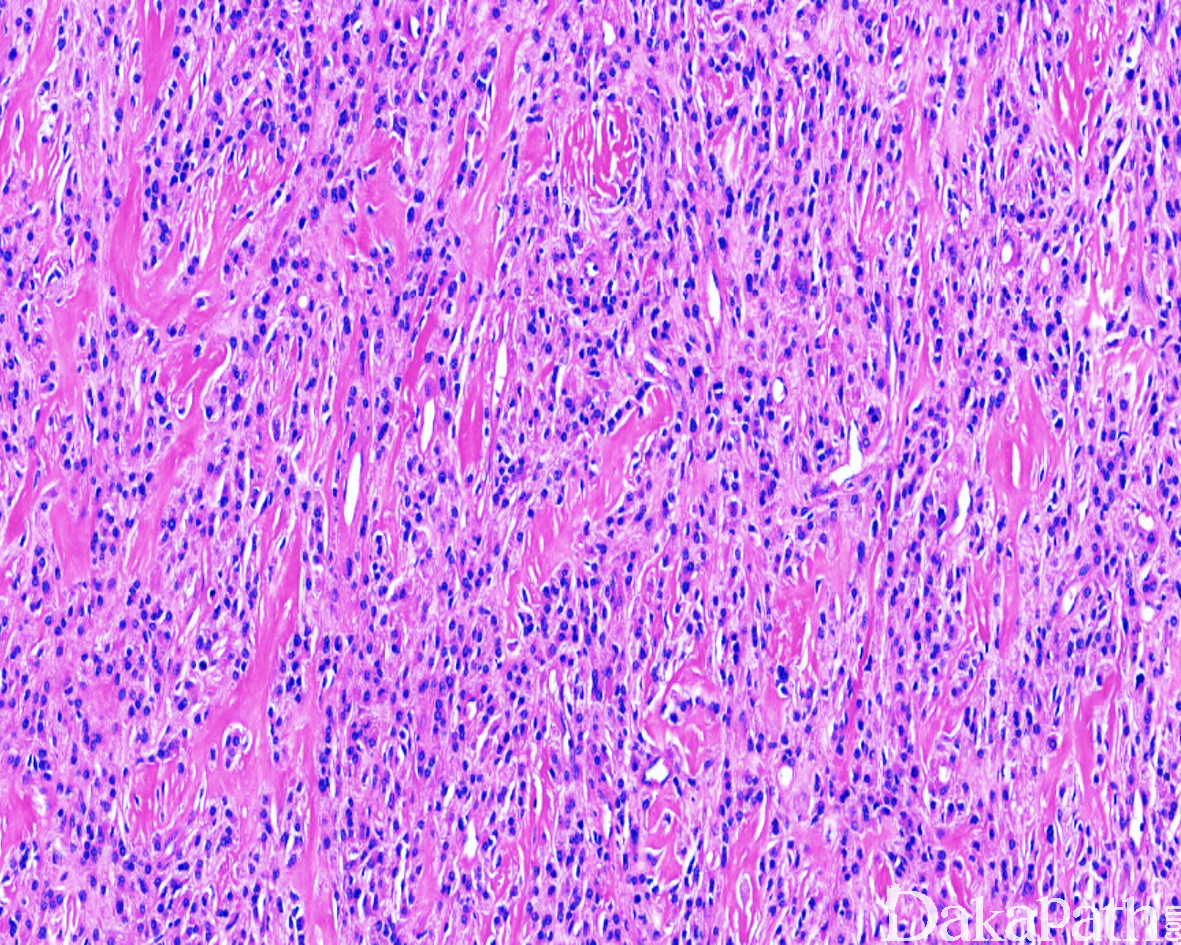

- 肿瘤的实质由多个大小不一、细胞密度不均的小叶组成,小叶内的瘤细胞呈交织索状、梁状、短束状、纤细的网格状排列,有时也可呈马赛克样排列;小叶间为粗细不等的纤维性间隔;

- 细胞圆形、卵圆形或短梭形,大小较一致,胞质淡染或呈嗜伊红色,核染色质细致,核分裂像一般较少见(<2/50HPF),无非典型核分裂象,罕见坏死;

- 瘤细胞间的基质多呈纤维黏液样,或伴多少不等的胶原纤维,部分区域显示明显的玻璃样变性,似骨样基质;